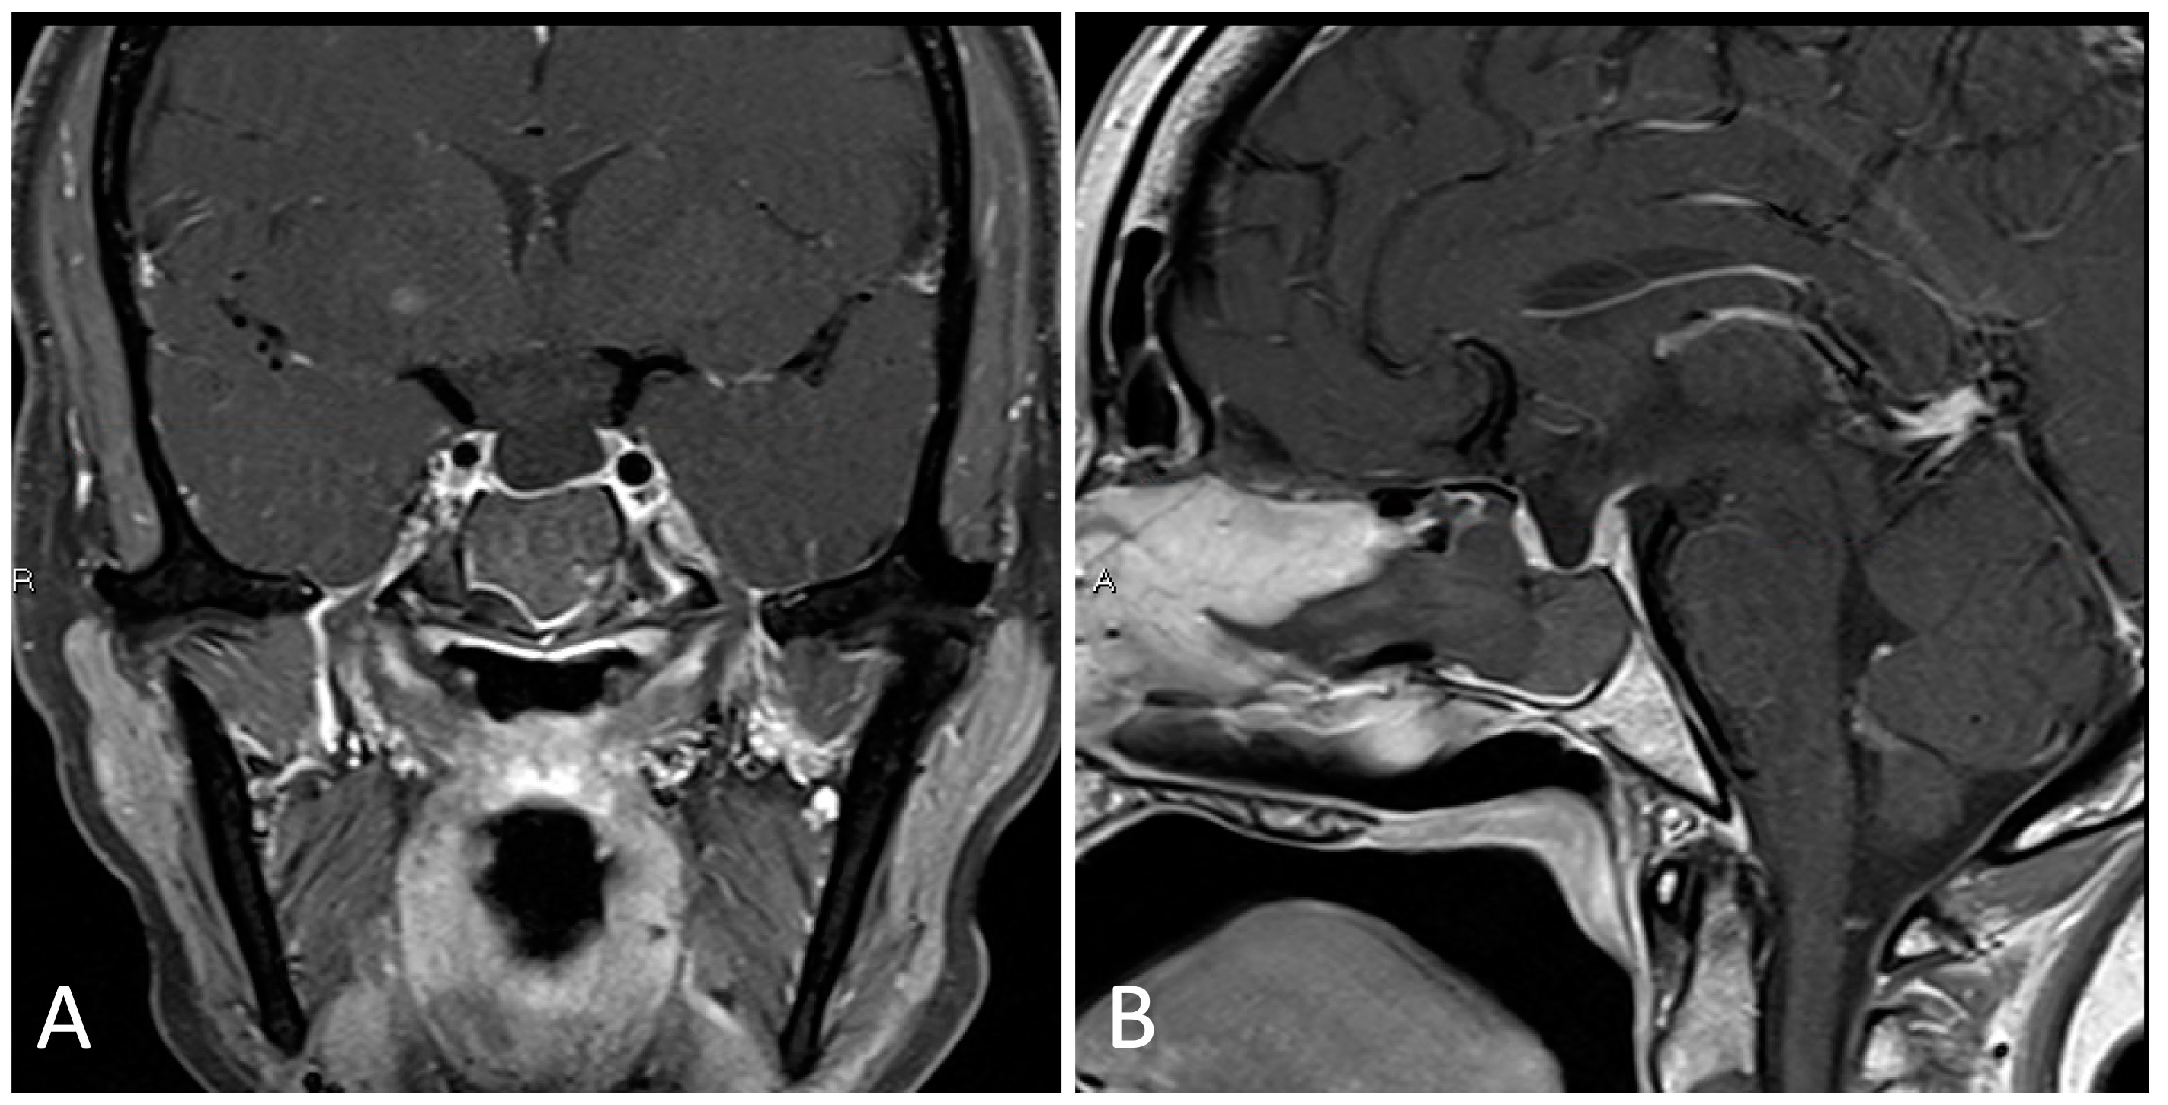

3.1.4. Illustrative Case

- Placement of a lumbar drain is advised at the start of surgery, or preoperatively, in cases where a high-flow CSF leak is anticipated, in order to reduce immediate postoperative intracerebral pressure (ICP) and offload excessive pressure on the skull base graft.

- Upfront harvest of a nasal septal flap may be useful for skull base reconstruction in cases of anticipated high flow CSF leak.

- The sphenoid limbus serves as an important landmark for the location of the optic nerves, bridging medial to the optic canal and forming the anterior border of the prechiasmatic sulcus.

- When approaching lesions within the suprasellar region, one should be mindful of the location of the optic apparatus (i.e., pre-fixed/post-fixed chiasm) as well as relevant neurovascular structures in the chiasmatic, lamina terminalis, interpeduncular, and prepontine cisterns.

- Craniopharyngiomas may be fenestrated into a natural CSF space, such as the basal cisterns and third ventricle, to reduce long-term cystic reaccumulation/recurrence.